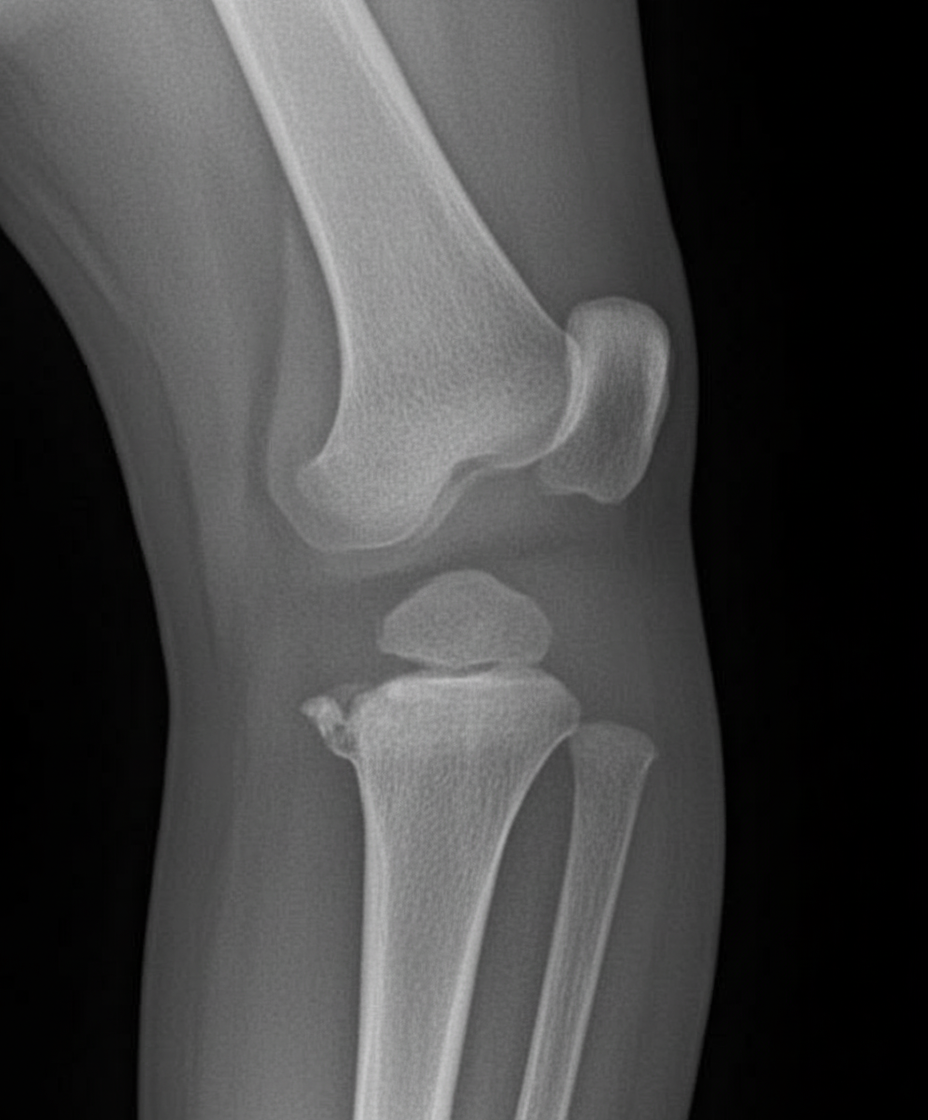

What is the possible diagnosis based on the provided X-ray image?

Explanation: ***Osgood-Schlatter disease*** - X-ray shows **tibial tuberosity fragmentation** and **irregularity** on lateral knee view, characteristic of this condition in adolescents - Presents as **anterior knee pain** below the patella with **tibial tubercle prominence** in active adolescents during growth spurts *Pellegrini-Stieda lesion* - Appears as **calcification** along the **medial collateral ligament** attachment at the medial femoral condyle on AP knee X-ray - Results from **chronic MCL injury** and shows **linear calcification** rather than tibial tuberosity changes *SLAP tear* - **Superior labrum anterior-posterior tear** of the shoulder **glenoid labrum** cannot be diagnosed on plain X-rays - Requires **MRI** or **MR arthrography** for visualization as it involves **soft tissue structures** not visible on X-ray *Segond fracture* - Shows as a **small avulsion fracture** of the **lateral tibial plateau** on AP knee X-ray - Associated with **ACL injury** and appears as a **small bony fragment** at the lateral joint line, not tibial tuberosity